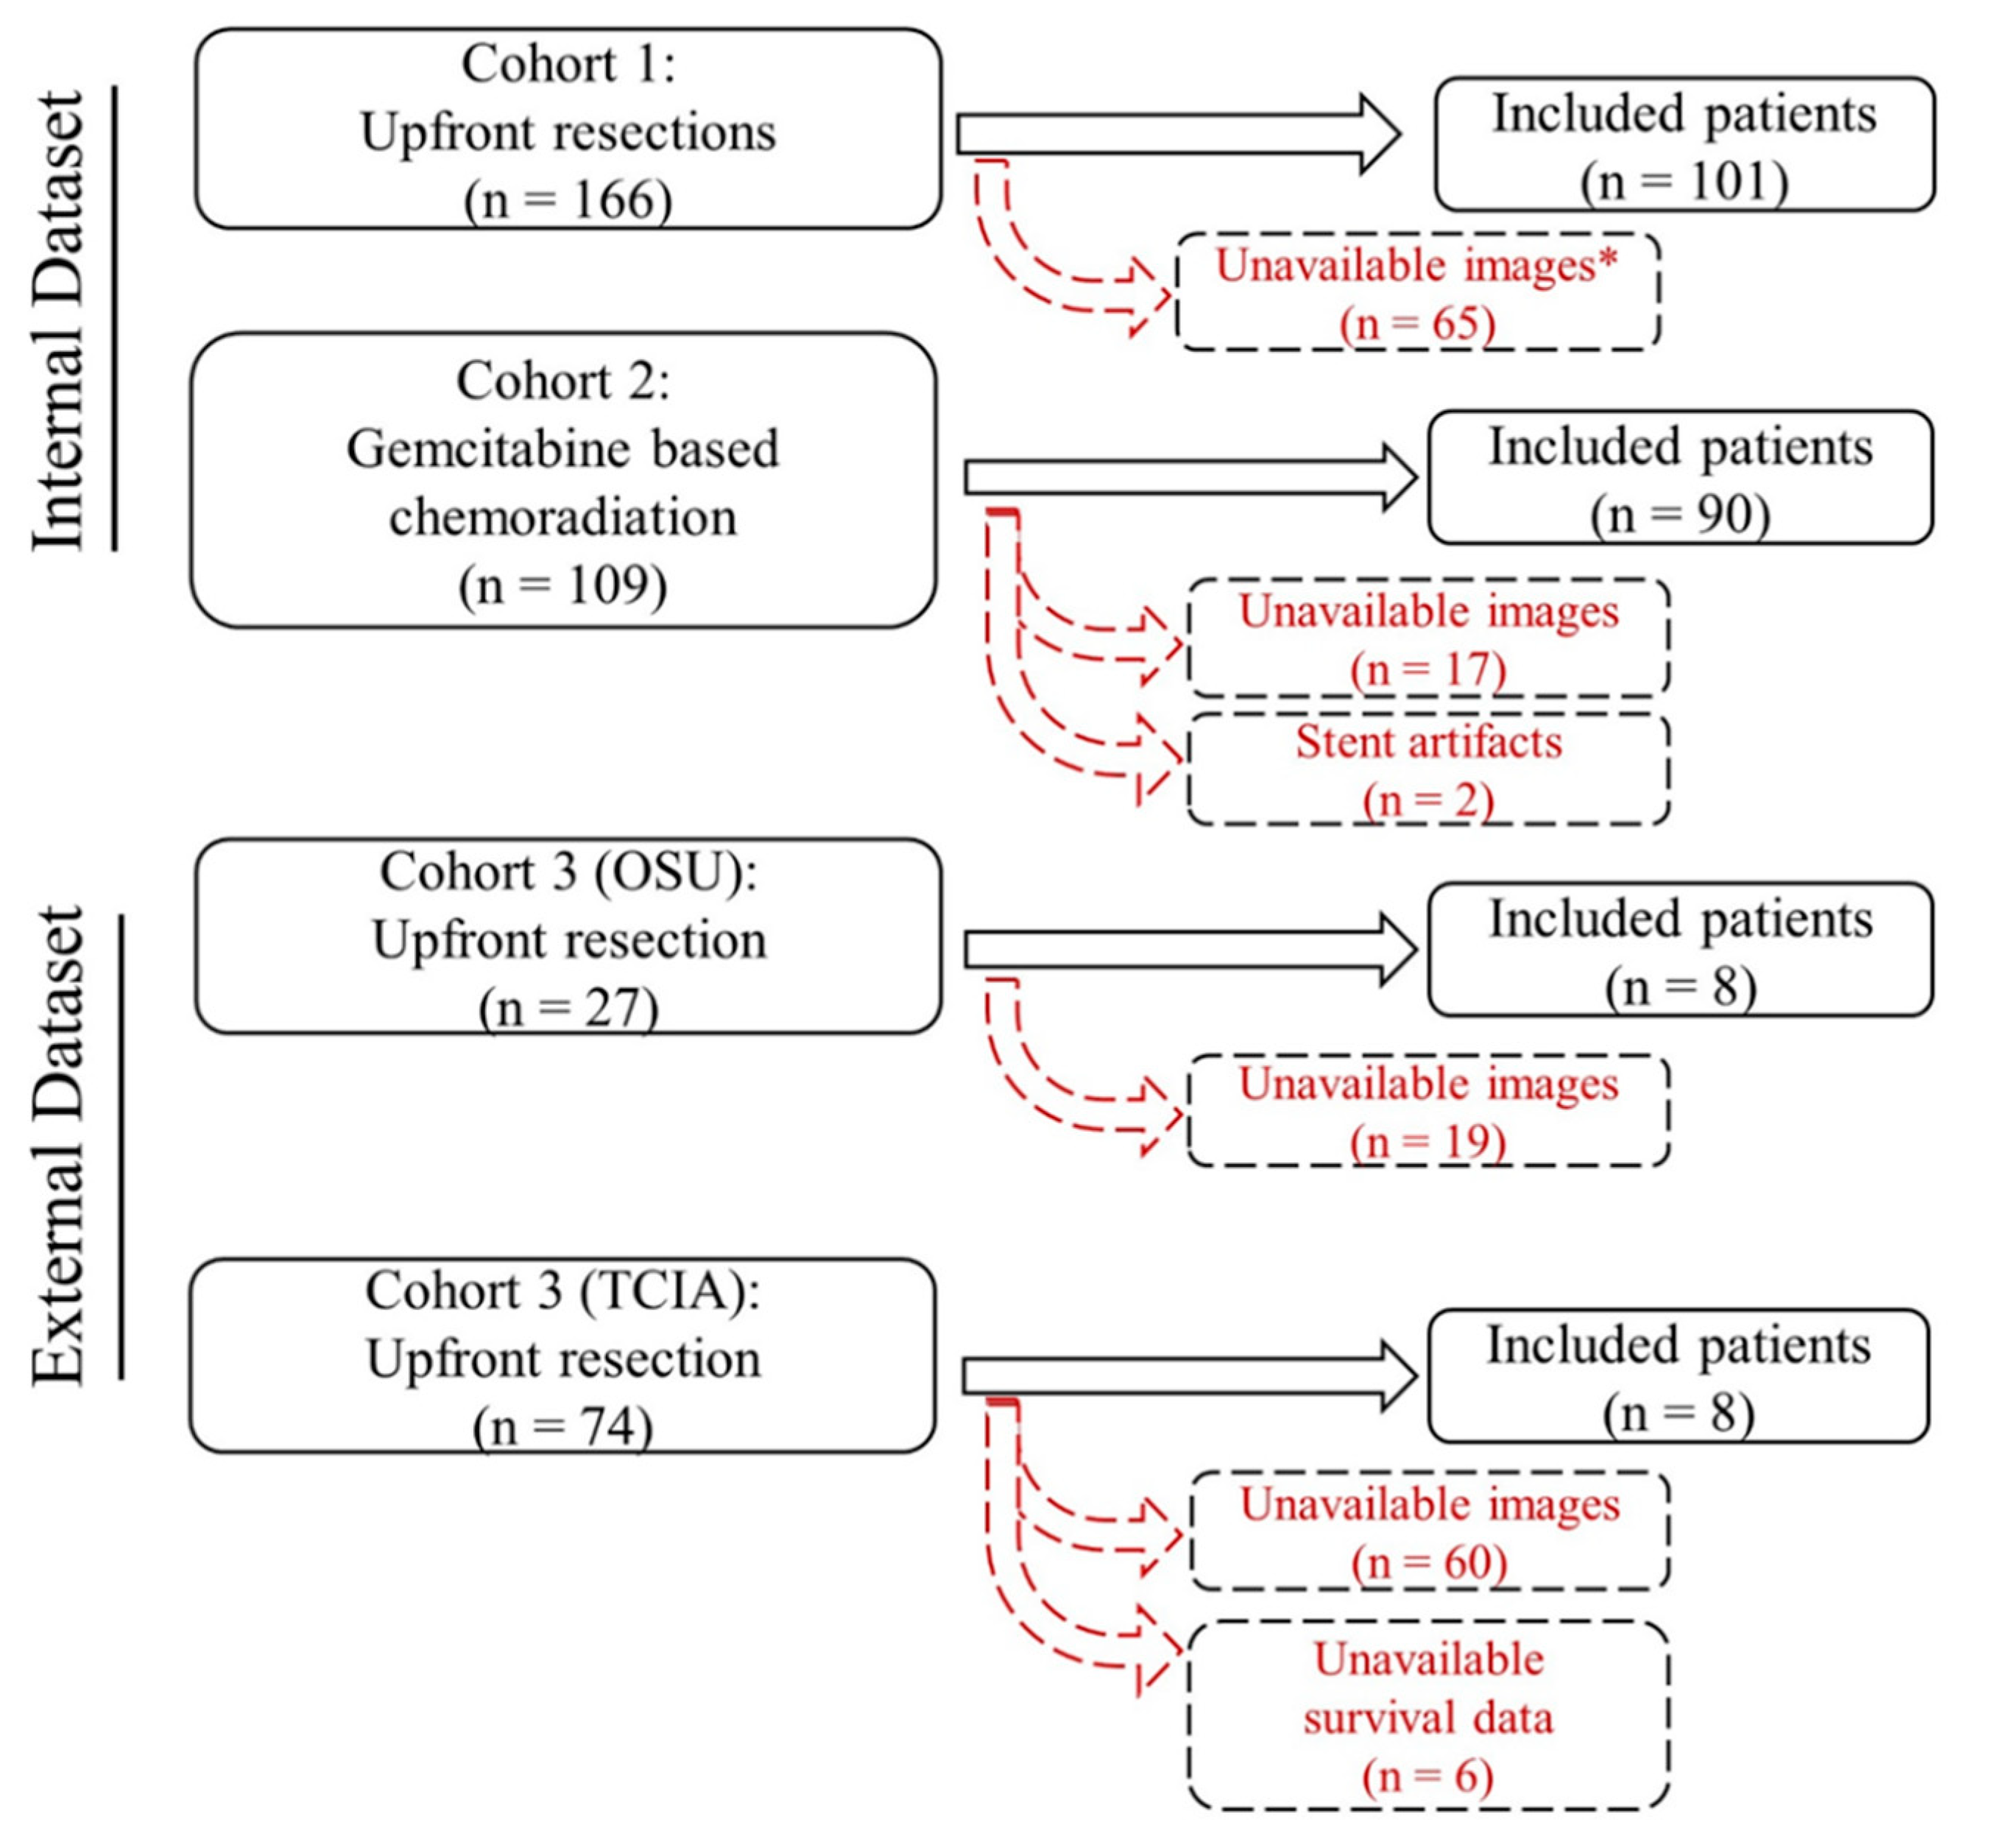

4.1. Patients